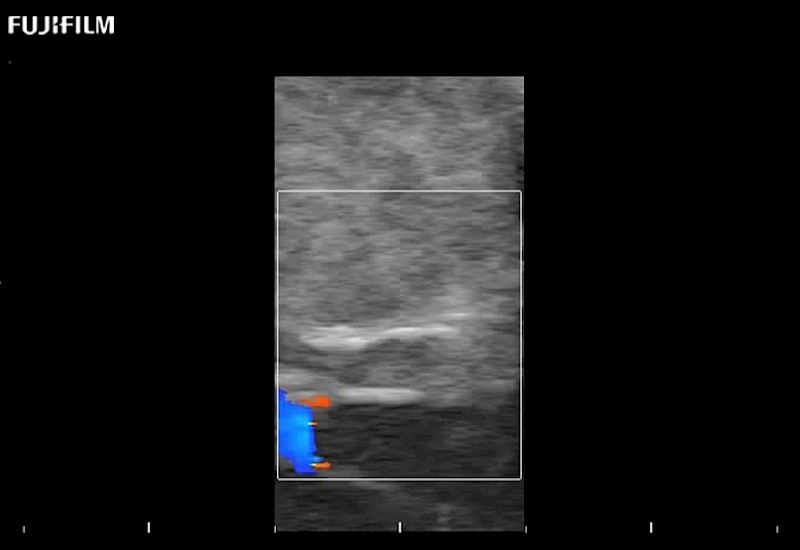

Exclusive 10mm side‐fire linear array transducer with 2.87mm diameter is ideal for real‐time visualization through and behind structures and instant, scalable definition of anatomy and vascularity including the ability to delineate and define tumor margins.

Guidance is the fundamental purpose for all of our surgical ultrasound technology. Fujifilm Healthcare is committed to designing tools that help neurosurgeons navigate inside the human body and provide the necessary information to immediately make critical surgical decisions.